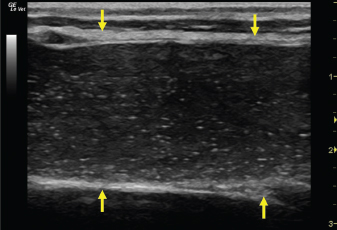

Fig. 4. Bi-dimensional ultrasonographic image of the right jugular vein in longitudinal section. The lumen of the vessel was occluded by a heterogeneous, non-cavitating, hypoechoic structure compatible with a thrombus (arrows).ç